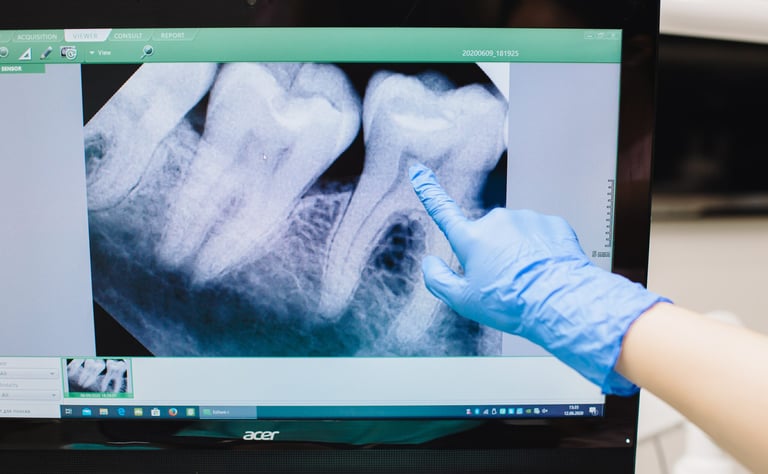

PERIAPICAL

Permite ver las zonas de interés con mayor definición y detalle, permite establecer una relación con estructuras adyacentes anatómicas o patológicas.

la serie periapical, es un estudio completo de los dientes y de sus estructuras mas cercanas.